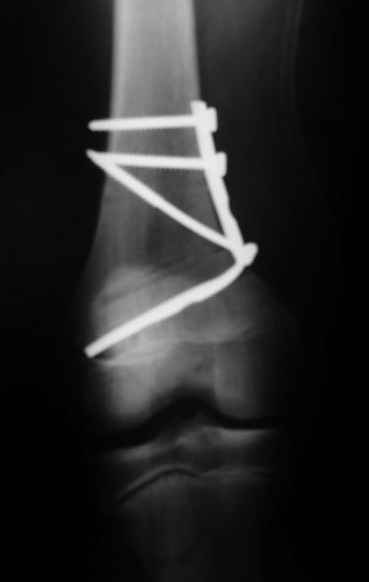

Как вариант решения прогрессирующей вальгусной деформации коленного сустава я бы предложил косую остеотомию дистального отдела бедра с фиксацией пластиной и компрессирующим винтом.

Взгляните на снимки , может быть это вам поможет.

Около 5 лет применяю этот тип дистальной остеотомии бедра для коррекции механической оси Н/К ( более 20 случаев) - достаточно эффективная операция.